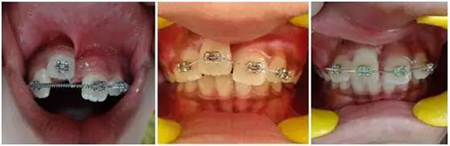

正畸牽引觀察其復位情況: 先觀察挫入的牙齒在未干預的情況下自發(fā)復位的情況。經過3周的觀察,牙12復位,但牙11沒有顯示出復位的跡象。因此,使用MBT托槽正畸牽引牙11復位。為了讓其沿正確的方向復位,使用橡皮圈以獲得緩慢持續(xù)的牽引力(圖3)。

(圖3)

正畸牽引5周后,牙齒復位到其原始位置,與其他切牙完全對齊(圖3)。開始嘗試血運重建。重新打開根管,使用次氯酸鈉和生理鹽水沖洗。然后插入無菌根管銼,并將其推到根尖處,以使血流進入根管。一旦血液到達釉牙骨質界,放置一個濕潤的無菌棉球靜置15分鐘,直到血凝塊形成,再放置約2-3mm的MAT在血凝塊上。在MAT上覆蓋一個濕棉球,隨后進行臨時修復。以后再替換為玻璃離子水門汀墊底和復合樹脂修復。復診時間為1、3、6、9和12月。正畸復位保留12周。然而,在這么長的保留期內還是復發(fā)了錯位,這也強調了在嚴重侵入的情況下長期復位的重要性,因為累及的牙齒周圍出現(xiàn)大量的牙槽骨喪失(圖 4)。